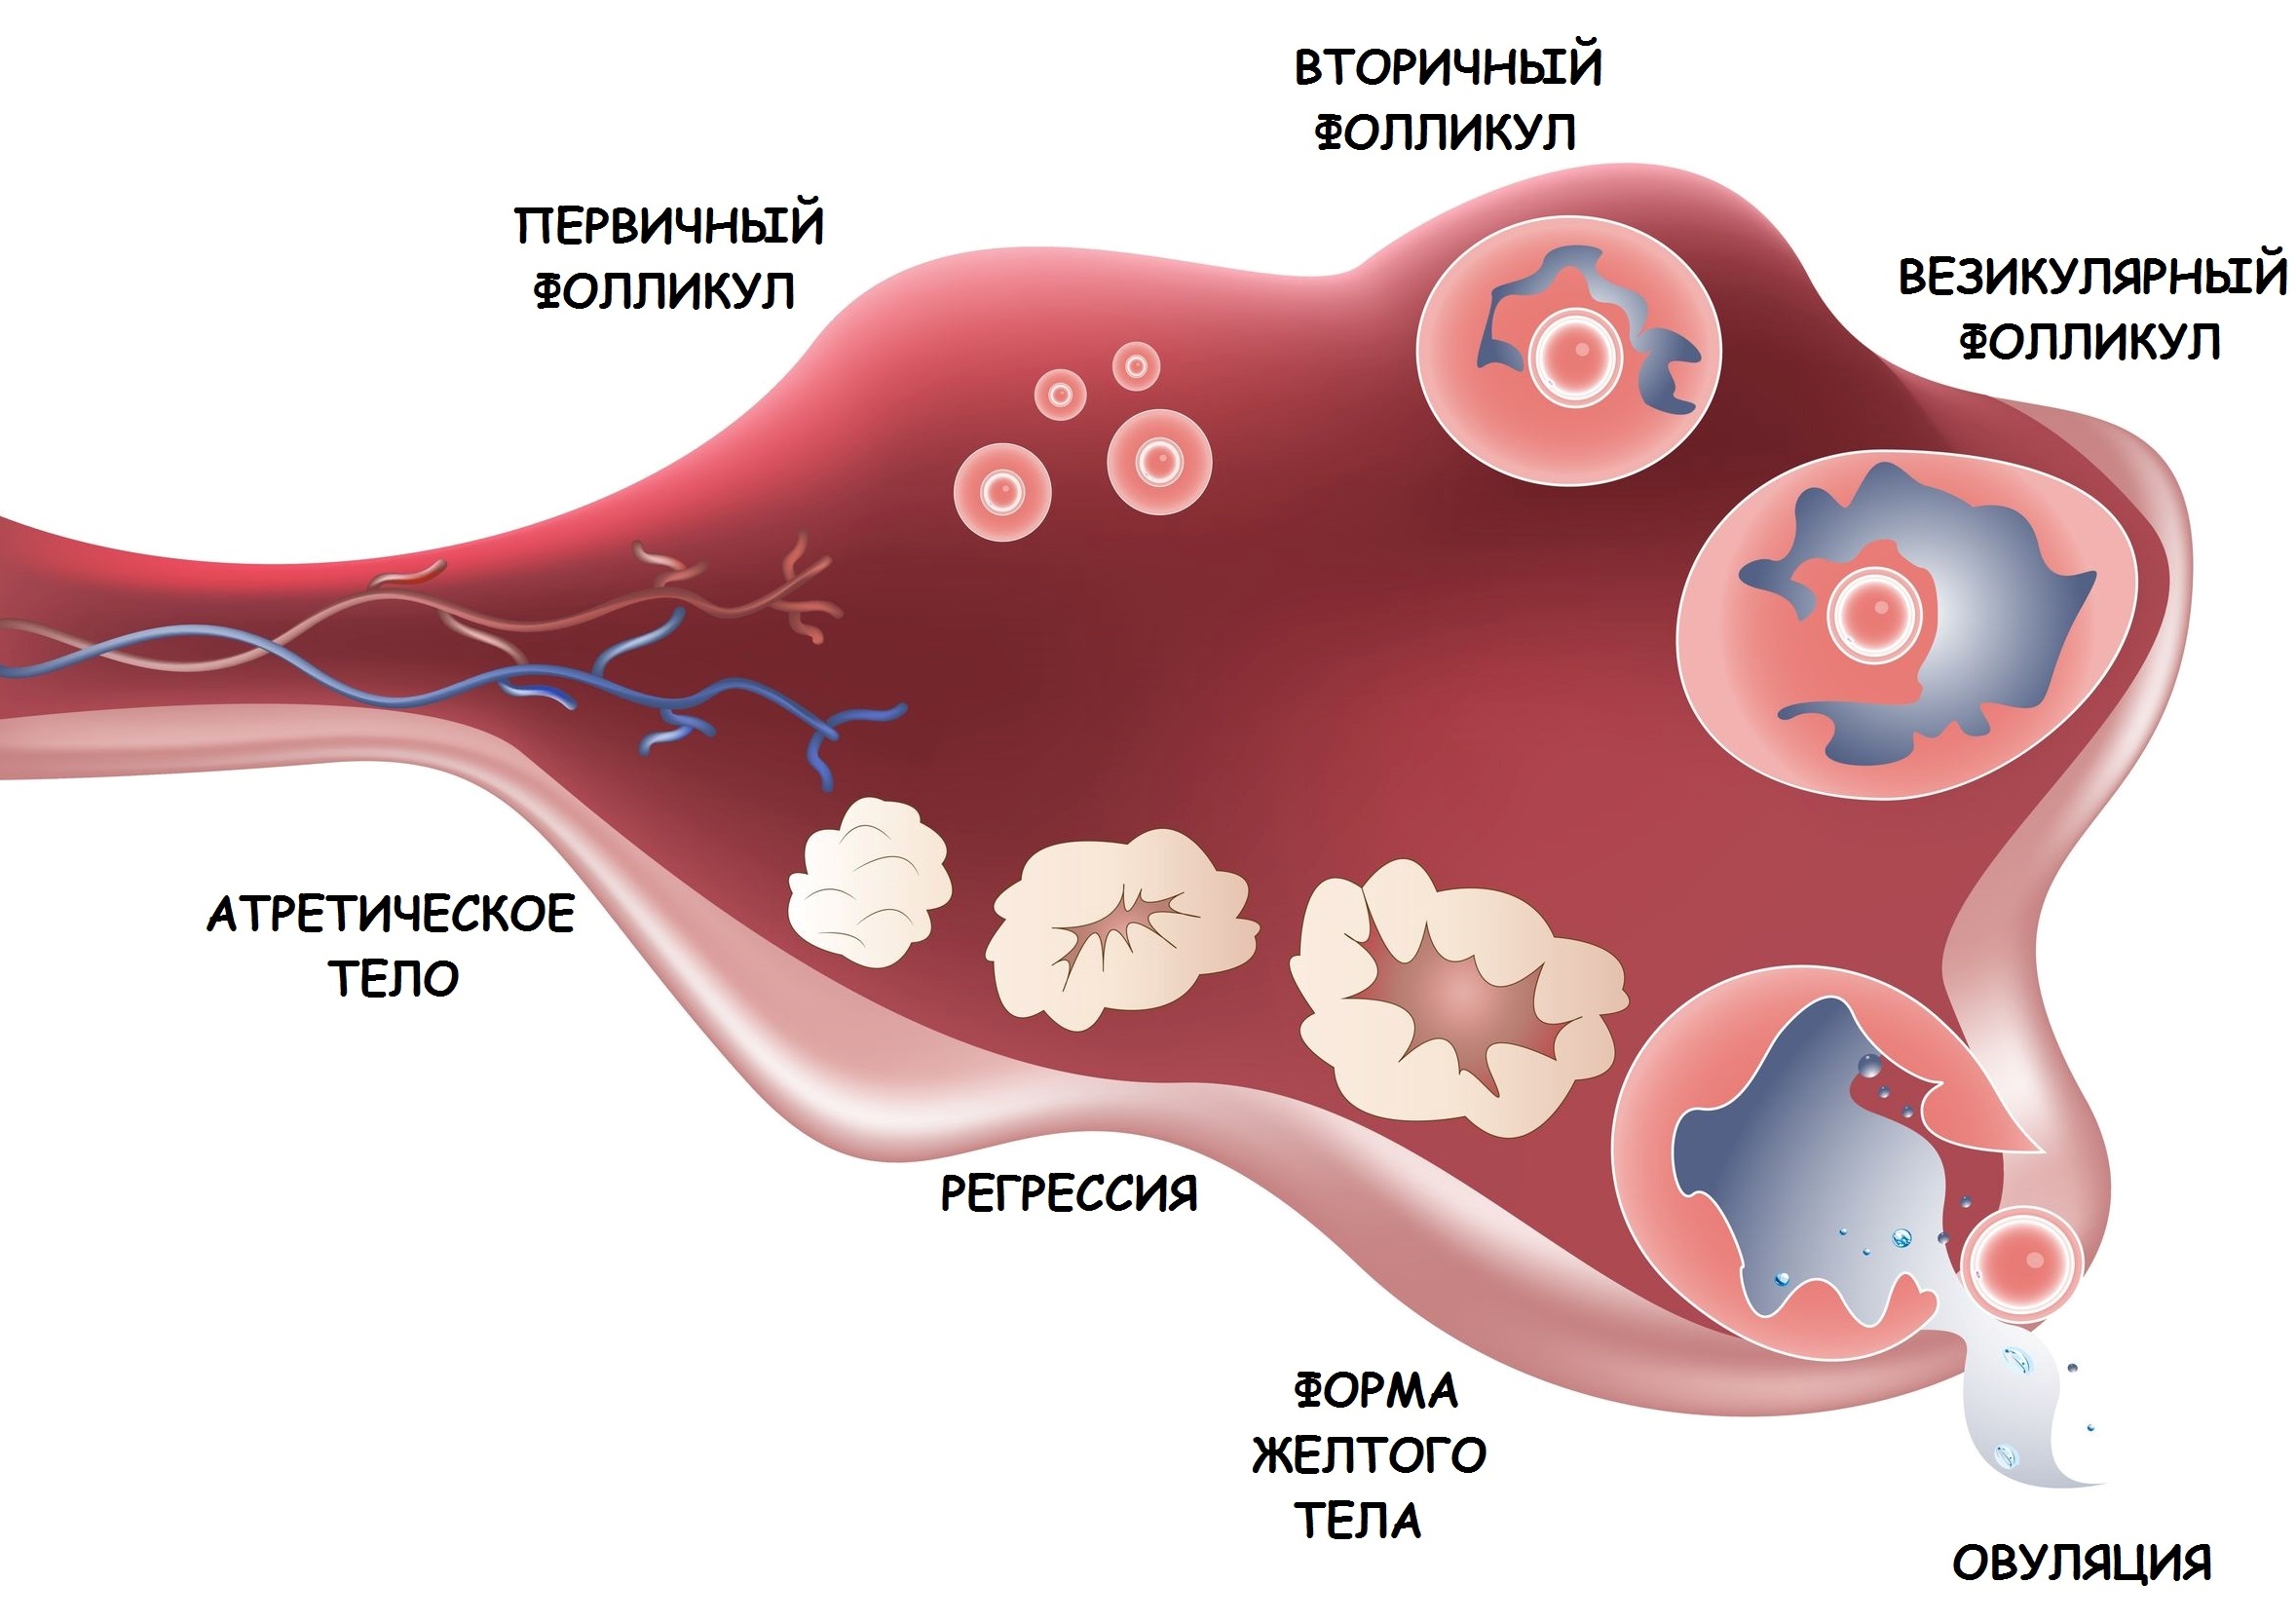

Созревание фолликула в яичнике: этапы и процессы